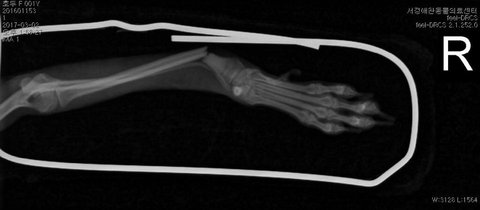

아래는 저희 아가 처음 병원간날 찍은 엑스레이 사진입니다..

정말 괜찮은줄 알았어요..

10일뒤에 보면 된다고 했으니까요..